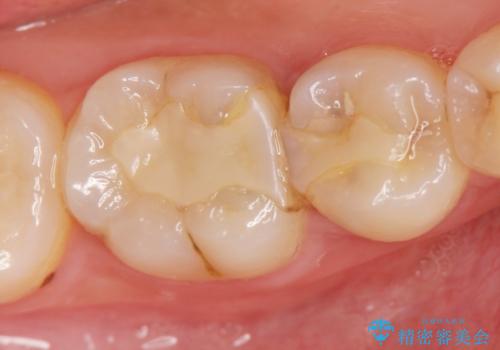

歯が黒くなってきた 虫歯のセラミック治療

- 以前虫歯治療を行い、詰めた箇所が黒く変色し不安になり検査を求めて来院されました。

X線撮影を行った結果、詰めた箇所の下部に虫歯の再発を認めました。